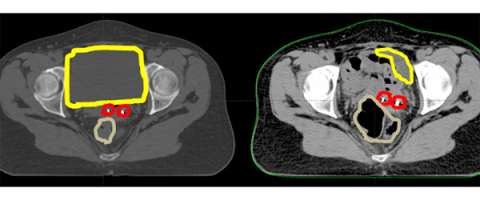

Here is an axial CT scan slice of an actual patient with her bladder full on the left and her bladder empty on the right. You can see that with the bladder (yellow) empty that additional bowel falls within the pelvis and that the marker seeds (red) are in a different place (also in part due to increased air in the rectum (brown). This example demonstrates the importance of daily image guidance and making sure that your bladder is consistently full during the course of your treatment.

CT Scan